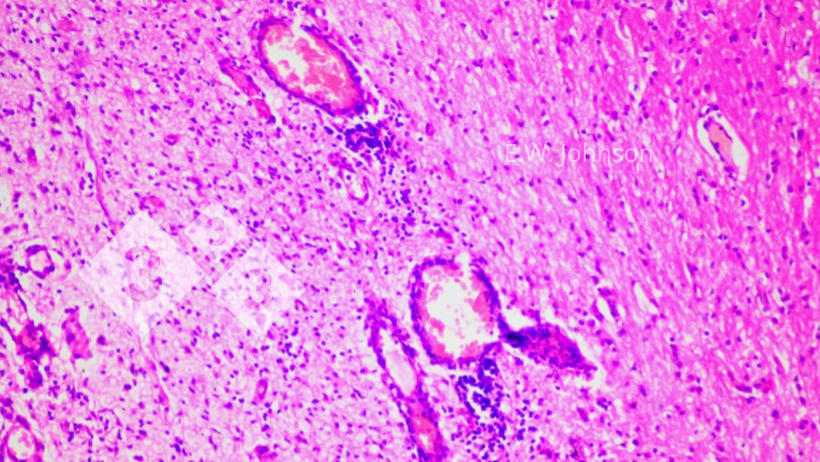

L'esame microscopico del cervello rivela meningoencefalite con cuffia (cuffing) perivascolare e gliosi (immagine 2) e infiltrazione delle meningi con cellule infiammatorie miste mononucleate e polimorfonucleate (immagine 3).